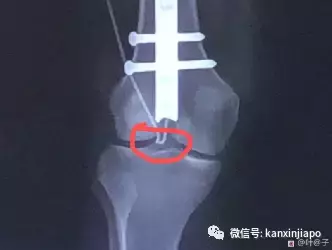

叶子签署的风险需知文件 本以为休养六周就可以回国,没想到噩梦才刚刚开始。 手术7天后的10月22号,医生通过X光片发现,叶子体内的F针已损坏,需要进行二次手术,将骨腔打开,换一根新的F针,不然会造成长短腿残疾。虽然频繁换针也会增加感染骨髓炎的风险和诸多后遗症,但叶子别无他法,只好在11月8日进行了修复手术。

经过第二次手术,叶子本以为一切已恢复正常。可是短短一周后的11月17日,X光显示右腿的F针又再次出现问题,钉子脱落,需要接受第三次开刀。这时,身体和精神的双重摧残已经让叶子濒临崩溃。 然而,事情并没有到此为止。第三次手术后不到一个月的时间,右腿的F针又出现了问题,无法正常运行,需要马上第四次开刀。

叶子在12月31号接受了第四次手术,将右腿F针的接收器取出,并更换新的。但手术还是以失败告终,右腿的F针仍然无法运行。目前,她左腿的F针还在运作,但右腿已经无法承受手术。

因为左腿F针运行正常,右腿F针损坏,叶子现在已经出现了长短腿的问题。